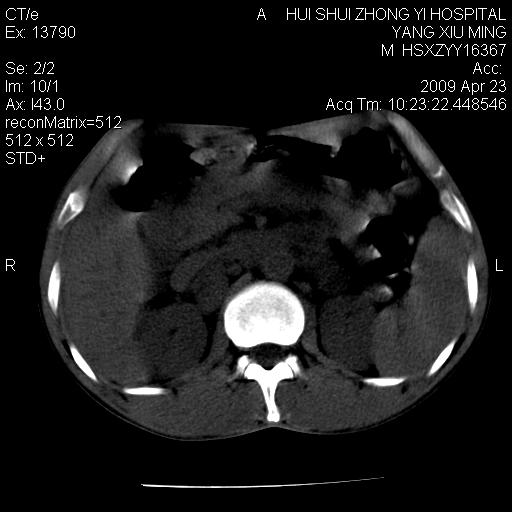

腹膜后淋巴结增大,转移、淋巴瘤?胰腺增大,胰腺炎?占位?颈部考虑增大淋巴结。建议腹部增强扫描。

缺少强化资料,暂考虑胰腺癌广泛转移.

连最基本的ct值都没有测        腹部的窗宽窗位太大了     影响诊断

黑!广泛淋巴结肿大不符合胰腺癌转移。胰腺周围淋巴结肿大致使胰腺看起来大。考虑淋巴瘤可能大。